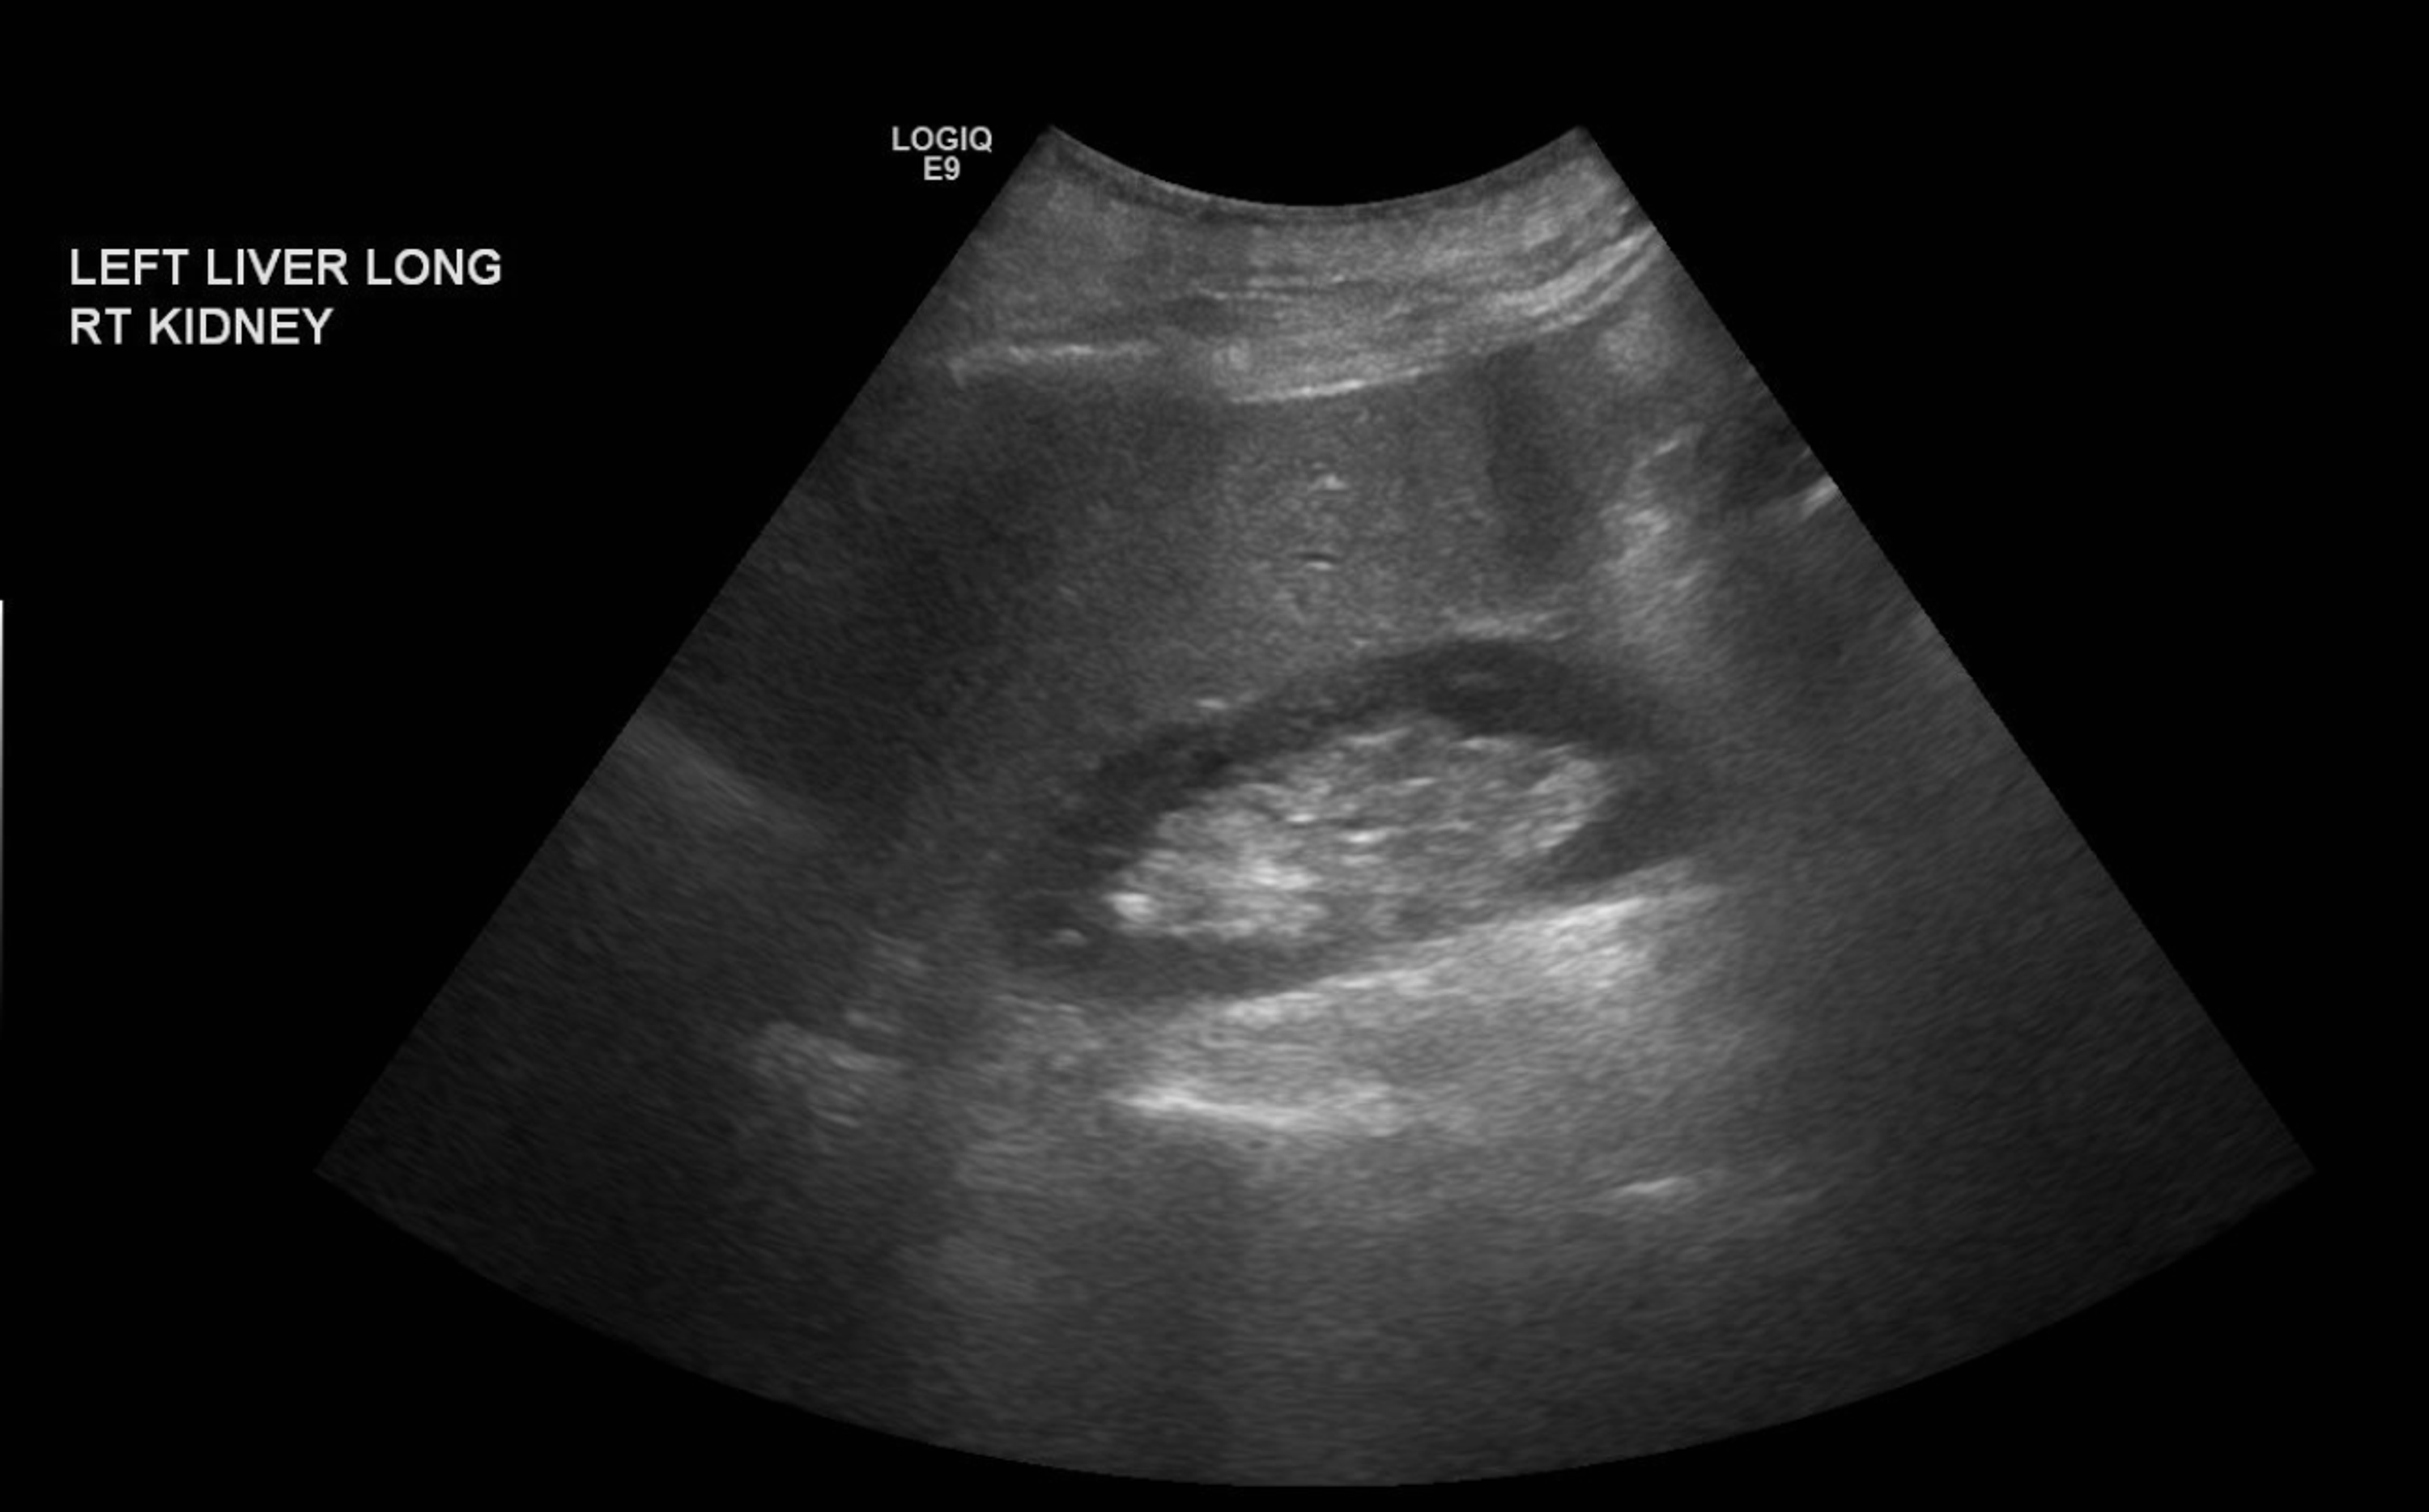

Cureus Lupus and the Liver A Case Study

Cureus Lupus and the Liver A Case Study Lupus And Liver Liver disease has been shown to be a common complication of sle. 21% of the patients were defined as having liver disease on the basis of. Find out the symptoms, treatments and tests for liver. Find out about the symptoms, causes, and treatments of lupus hepatitis,. Learn how lupus can affect the liver and other organs of the digestive system,. Lupus And Liver.